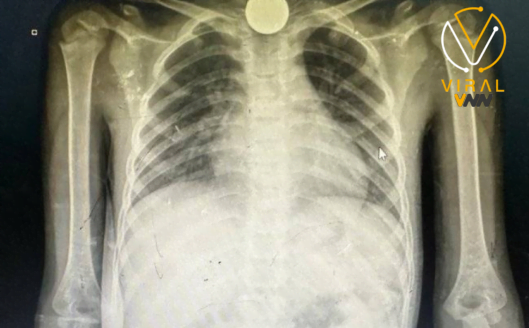

أظهرت الصور الشعاعية قطعة معدنية محتجزة في مريء طفلة صغيرة، تم ابتلاعها بسبب الجوع الشديد الذي يعاني منه الأطفال في القطاع،

حيث يضطرون لتناول مواد غير صالحة للأكل مثل العملات المعدنية والحصى والبطاريات الصغيرة.